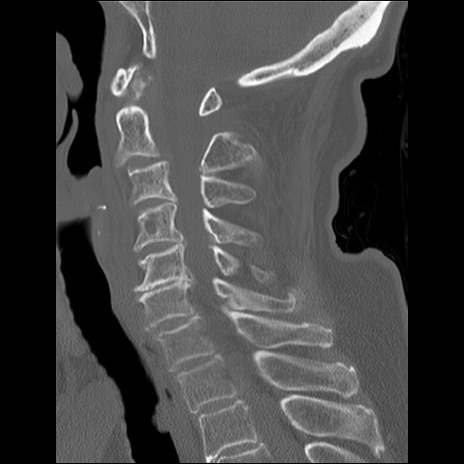

症例48 頚椎CT(矢状断像)

頚椎CT